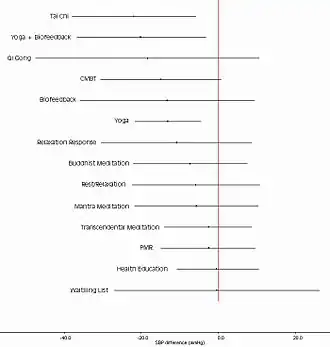

A 2013 statement from the American Heart Association said that Transcendental Meditation could be considered as a treatment for hypertension, although other interventions such as exercise and device-guided breathing were more effective and better supported by clinical evidence.[122]

Transcendental Meditation may reduce blood pressure, according to a 2015 review that compared it to control groups. A trend over time indicated that practicing Transcendental Meditation may lower blood pressure. Such effects are comparable to other lifestyle interventions. Conflicting findings across reviews and a potential risk of bias indicated the necessity of further evidence.[125][126]

In June 2007, the United States National Center for Complementary and Integrative Health published an independent, peer-reviewed, meta-analysis of the state of meditation research, conducted by researchers at the University of Alberta Evidence-based Practice Center. The report reviewed 813 studies involving five broad categories of meditation: mantra meditation, mindfulness meditation, yoga, tai chi, and qigong, and included all studies on adults through September 2005, with a particular focus on research pertaining to hypertension, cardiovascular disease, and substance abuse. The report concluded: